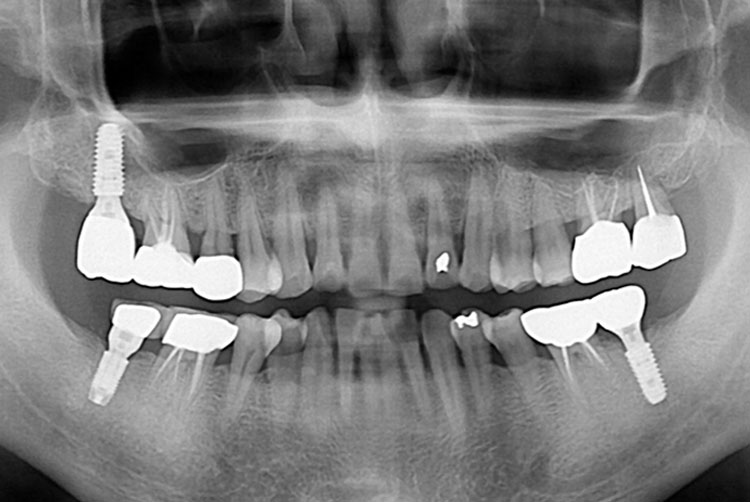

[임플란트] 임플란트

치료전 : 2017-06-16

세종치과는 많은 환자와 다양한 케이스를 바탕으로 항상 편안한 임플란트 수술을 제공하고자 노력하고,

오래동안 튼튼히 쓸 수 있는 임플란트 수술을 가장 큰 목표로 삼고 있습니다.